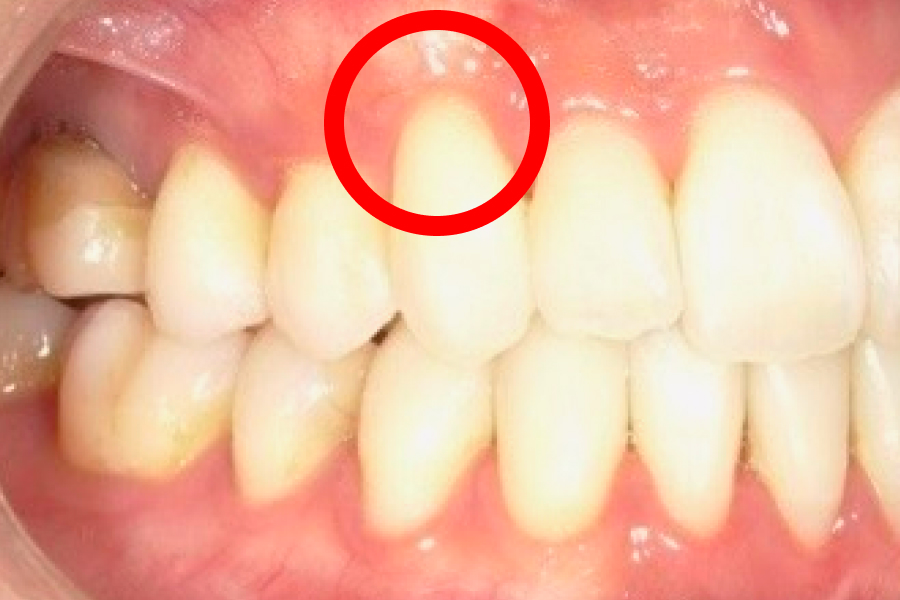

歯肉退縮が進むと、まず歯ぐきが下がって本来覆われていた根元が見えるため歯が長く見えるようになり、ついで歯根が露出することで冷水やブラッシングでしみる知覚過敏や根元のむし歯(歯根う蝕)、歯間が広がって食片が挟まりやすい・黒三角が目立つといった審美面の問題が生じます。

歯肉弁移動術

歯肉退縮部の周囲に小切開を加え、血流を保ったまま歯肉弁を丁寧に剥離し、歯冠方向へ移動させて露出した根面を覆い、縫合で固定する治療です。歯肉の厚みと付着を確保することで、これ以上の後退を抑え、知覚過敏や審美性を改善します。

歯茎下がり症例